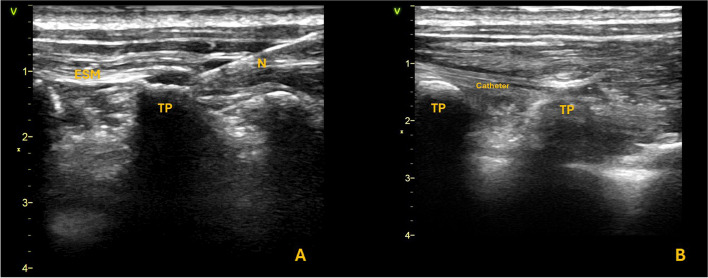

Abstract Image